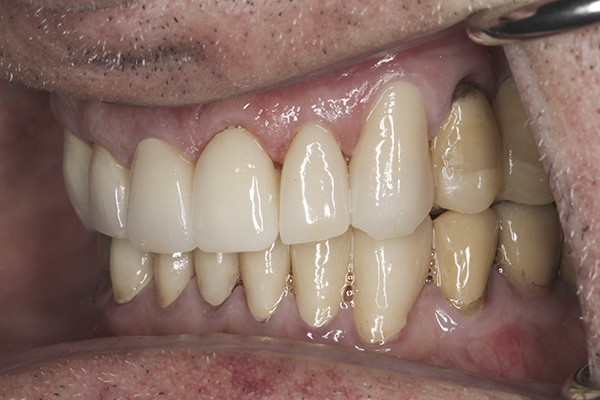

(32.) Postoperative right lateral, open view.

Figure 32

(35.) Postoperative right lateral, closed view.

Figure 35

Based on examination of the mounted models, it was decided to treat the patient in centric relation and an additive equilibration approach was used to idealize the planes of occlusion. On the articulator, the patient’s first point of contact in centric relation was the starting point and an additive equilibration technique was implemented, building the teeth to meet ideally at the patient’s first point of contact. A diagnostic wax-up was completed on the mounted models to determine where the anterior and posterior teeth needed to be in space. A template from the wax-up was used to fabricate the anterior provisional restorations. The anterior teeth were restored with full-coverage restorations, creating ideal stops between the lower incisal edges and upper cingulums. The maxillary incisal edges were placed to provide proper phonetics and an acceptable esthetic outcome, while still working within the envelope of function. All of these parameters are worked out in the provisionals prior to moving forward with definitive restorations. With the anterior provisionals in place, posterior composite tops were bonded to his existing dentition, creating ideal centric stops on the posterior teeth. The anterior and canine guidance was developed, resulting in immediate separation of the posterior teeth during all excursive movements (Figure 17 through Figure 28). Once the author and patient were happy with the function, esthetics, phonetics, and comfort of the provisionals, an impression of the approved provisionals was taken and sent to the laboratory to use as a guide in the fabrication of the final anterior crowns. With the final restorations delivered, the patient was extremely happy with his new smile. Most importantly, proper anterior and canine guidance in harmony with his envelope of function was achieved, which resulted in comfortable function and immediate separation of the posterior teeth during protrusive and lateral excursions (Figure 29 through Figure 42).